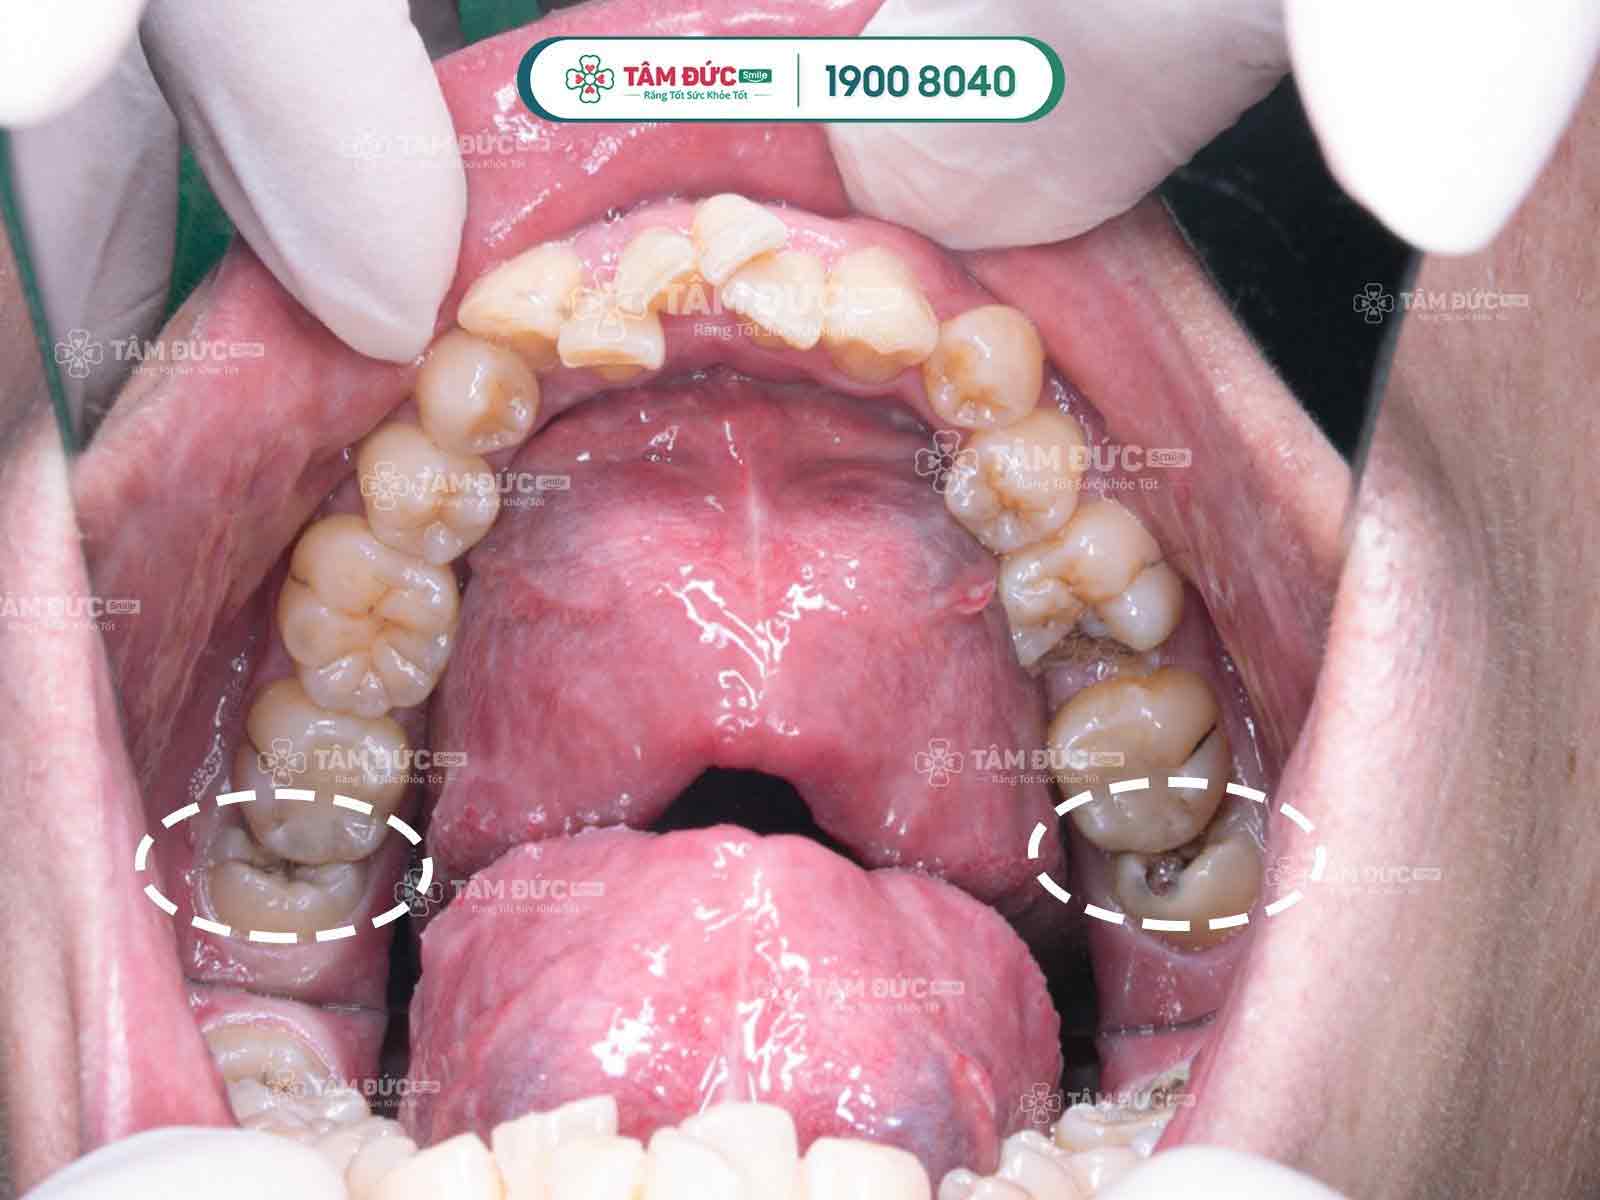

Răng khôn mọc lệch và bị sâu

Lợi trùm răng gây đau

Khi răng khôn mọc nghiêng thức ăn dễ kẹt vào kẽ răng, điều này khiến việc vệ sinh răng miệng gặp khó khăn, lâu dần tạo điều kiện để vi khuẩn sinh sôi, phát triển đục khoét vào men răng, dẫn đến tình trạng sâu răng, có thể gây viêm nhiễm làm răng khôn đau nhức dữ dội.

Răng khôn mọc lệch gây đau

Răng khôn mọc lệch đâm vào răng kế cận

Răng khôn mọc ngầm thường có hiểu hiện làm nướu sưng tấy, viêm đỏ, khó há miệng. Vì xương hàm không có đủ vị trí nên nó sẽ đâm sang răng bên cạnh, nó sẽ làm chiếc răng khỏe mạnh kế bên dần bị tiêu hủy, lung lay có thể dẫn đến sâu, nặng hơn nó sẽ khiến chiếc răng này bị xô đẩy chèn ép và rụng đi gây mất răng. Răng khôn mọc lệch, ngầm thường gây ra những cơn đau răng khôn âm ỉ kéo dài trong khoản 2 tới 3 ngày.